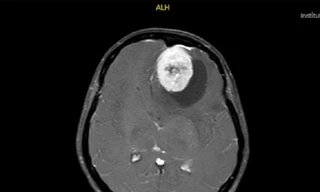

PGS.TS Lương Ngọc Khuê cho biết tại Bệnh viện Bạch Mai, 50-60% những bệnh nhân sau mắc COVID-19 với triệu chứng hô hấp kéo dài đến khám được chụp X-quang hoặc chụp cắt lớp vi tính lồng ngực thấy có tổn thương; sốt nhẹ, khó thở, mệt mỏi, đau cơ, khớp, rụng tóc, xơ phổi, tim đập nhanh hoặc đánh trống ngực, rối loạn nội tiết, huyết học bị huyết khối…

“Có trường hợp xuất hiện rối loạn tiêu hóa: ăn không ngon miệng, chán ăn, đau dạ dày, tiêu chảy; buồn nôn, nôn, đau thượng vị; rối loạn vị giác hoặc khứu giác, phát ban. Các triệu chứng về tâm thần như: rối loạn tâm lí, giảm sự tập trung, lo âu, trầm cảm, bồn chồn, rối loạn giấc ngủ, mau quên, không tập trung. Một số người xuất hiện tình trạng não sương mù, nhận thức kém, đọc chậm, giảm trí nhớ ngắn hạn, thay đổi tâm trạng”, TS Khuê thông tin.